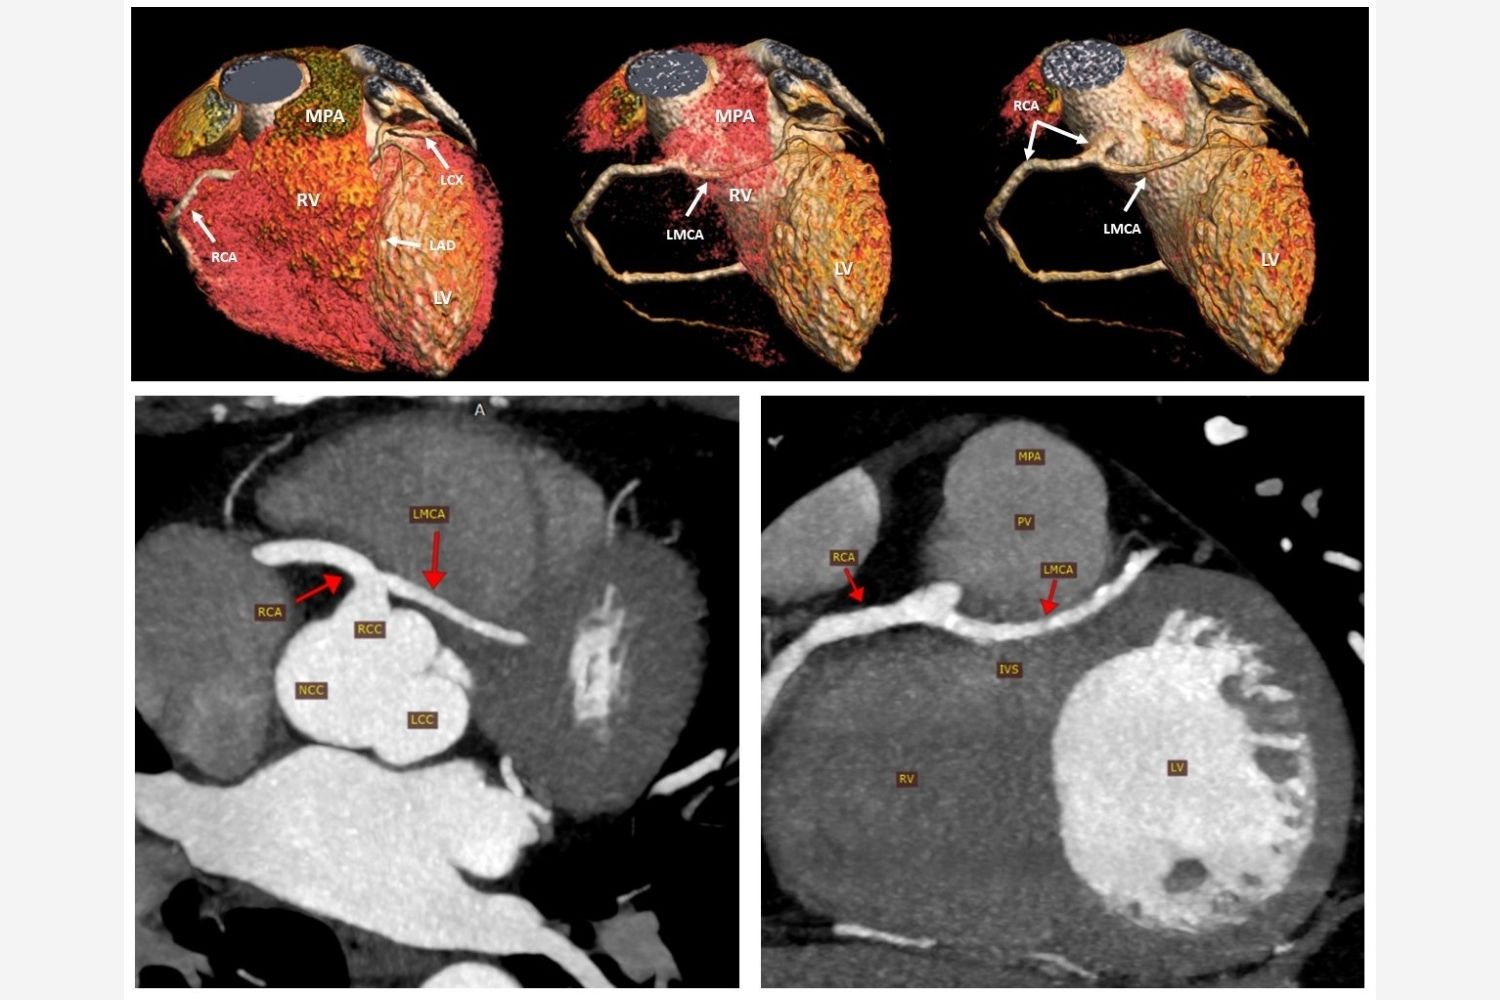

Image of the Week - 3 July 2024

Doctor Mohsin Mantoo

Doctor Sourabh Agstam